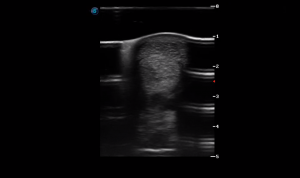

SIMON Ultrasound Database

This ultrasound database is a free resource for students and doctors!

Our collection includes videos of dogs, cats, horses, cows, humans, and many other species!